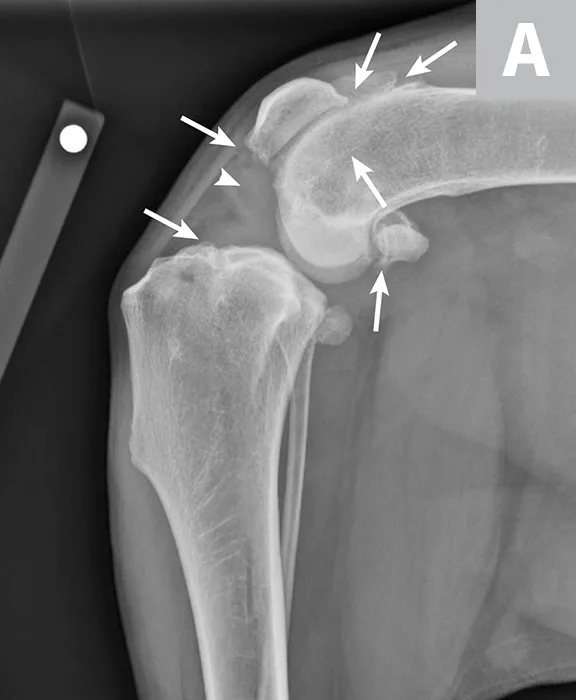

Labeled lateral and craniocaudal radiographs of right stifle showing pathologic features secondary to CCL rupture and medial meniscal tear.

FIGURE 2

Mediolateral (A) and craniocaudal (B) radiograph projections of a 3-year-old spayed mastiff with right CCL rupture and medial meniscal tear. Osteophytes are present on the femoral condyles, patella, fabellae, and tibial plateau (arrows). There is increased soft tissue opacity in the joint space consistent with joint effusion (arrowhead). In addition, there is cranial displacement of the tibia relative to the femur on the lateral projection. These signs combined are consistent with CCL rupture.